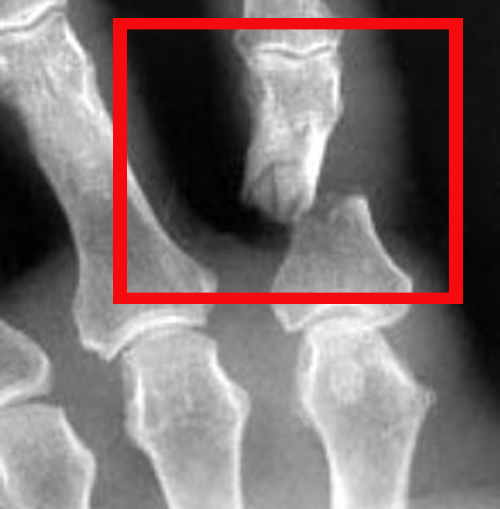

Диагностировать перелом пальцев руки у взрослых очень просто и чаще всего определить перелом можно самостоятельно. Но со 100% вероятностью установить закрытый перелом можно только используя рентген. Что же касается симптомов, то прежде всего это резкая боль, опухоль и гематома (кровь в поврежденном пальце скапливается в результате повреждений сосудов).

Перелом пальца со смещением характеризуется такими симптомами как сильное кровоизлияние в зоне перелома (повреждённый палец может посинеть), а так же сильно ограничивается подвижность травмированного пальца (чаще всего пациенты не могут сжать кисть в кулак или полностью разогнуть палец). Главным симптомом перелома со смещением является очевидная деформация.